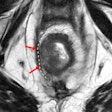

Imaging sheds light on complex cases of penile trauma